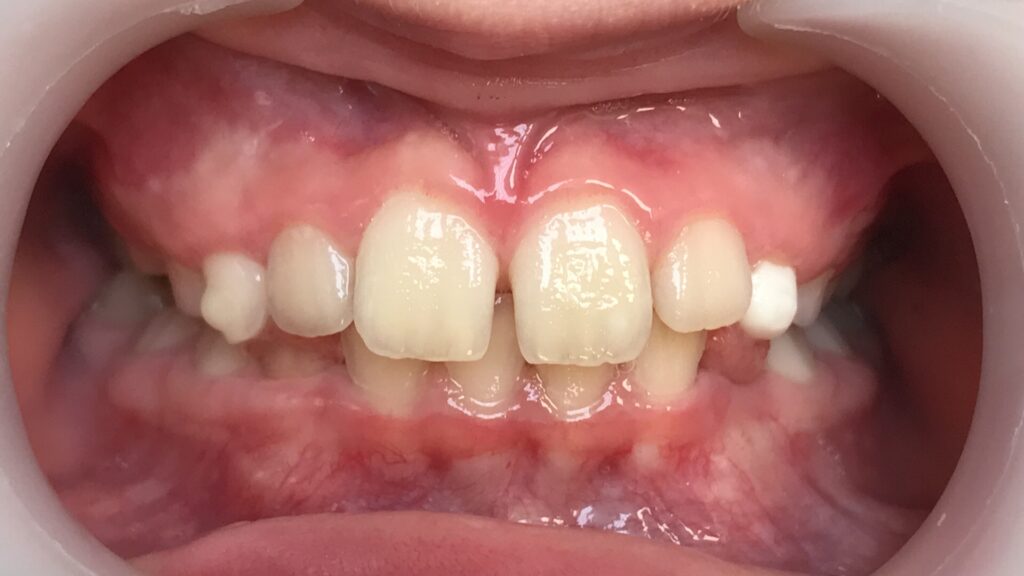

Un cas de recouvrement trop important avec bruxisme sévère :

La photo intermédiaire permet de voir que la situation en denture mixte était bien plus favorable qu’au départ. Quelle dentition aurait eu ce patient si on l’avait traité seulement à 12 ans ? et toutes les tensions dans son corps qui accompagnent ce genre de cas auraient surement perturbé sa croissance générale.

Photos à 6 ans, 9 ans et 15 ans